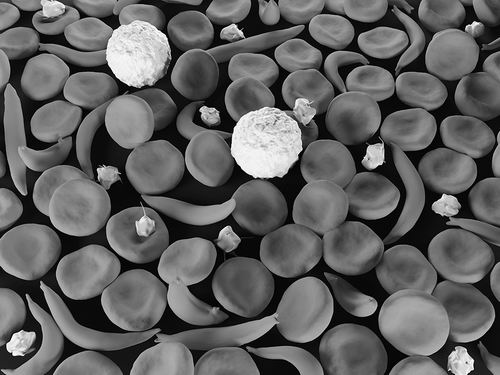

图片来源:iStock